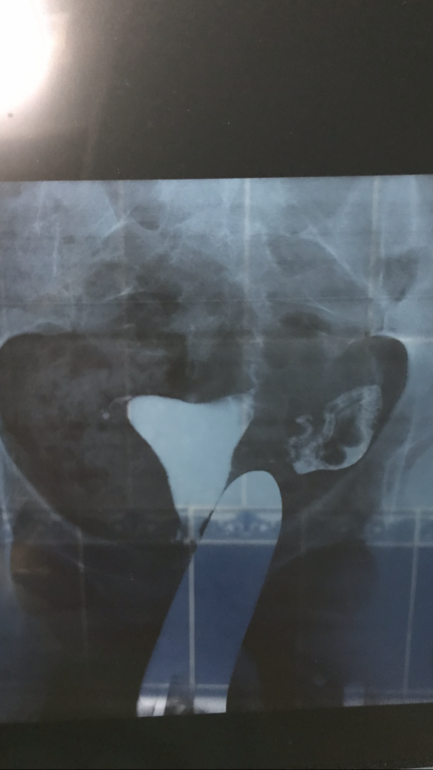

Можно планировать то? С такими снимками

Можно с такими снимками вообще планировать ?(((((